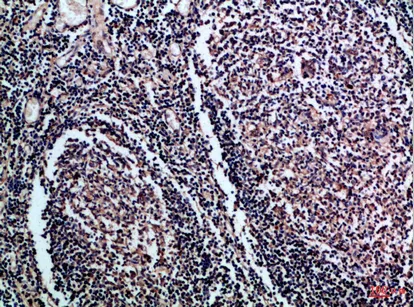

CD158f1/2 Rabbit Polyclonal Antibody($99/20μL)

Cat: APRab08227

Size1:20μL Price1:$99

Size2:50μL Price1:$118

Size3:100μL Price2:$220

Size4:200μL Price3:$380

Application:IHC-P,IF-P,IF-F,ICC/IF,ELISA

Reactivity:Human,Rat,Mouse

Conjugate:Unconjugated

Optional conjugates: Biotin, FITC (free of charge). See other 26 conjugates.

Gene Name:KIR2DL5A/B CD158F CD158F1/2 KIR2DL5 IR2DLX